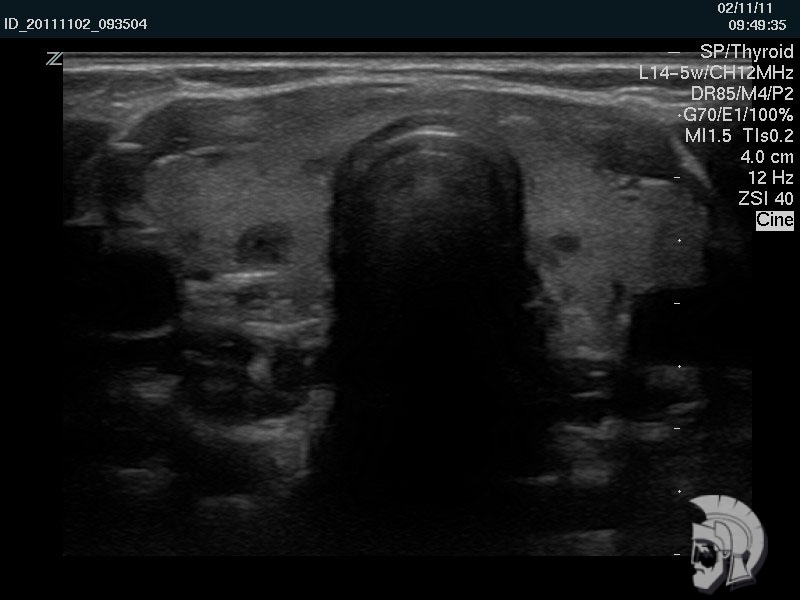

Фото щитовидной железы. Аутоиммунный тиреоидит у мужчины 39 лет. Определяется грубая неоднородность эхо-структуры долей щитовидной железы |

Обратите внимание на совершенное качество фотографий, свидетельствующих об экспертном классе аппаратов УЗИ!

Использование ультразвуковых аппаратов экспертного класса с режимами энергетического допплера и цветового допплера позволяет врачам Курортной клиники мужского здоровья выявить патологические изменения щитовидной железы на ранних этапах.